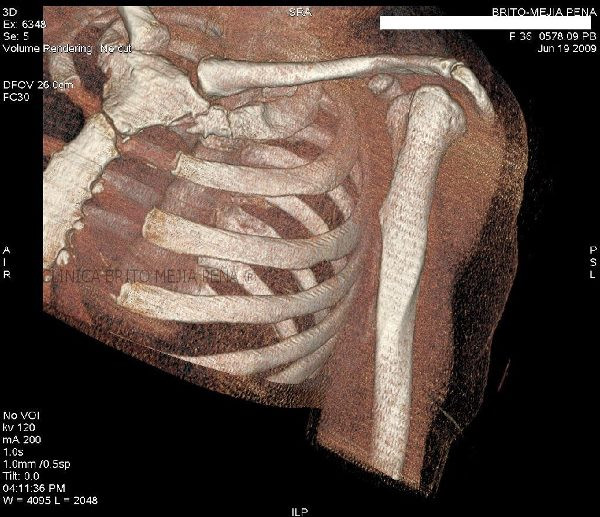

Fracturas en esternón y costillas